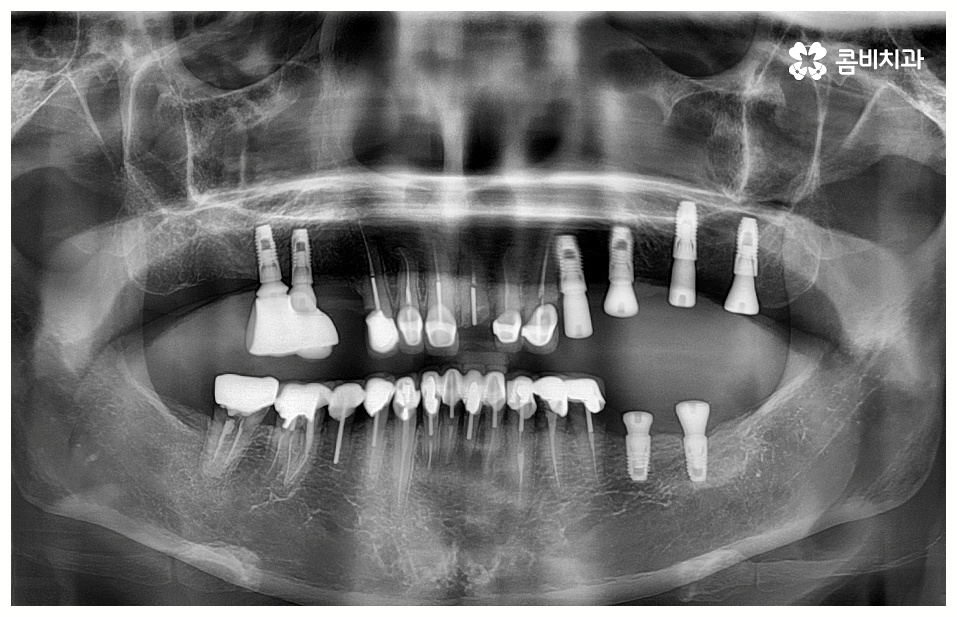

임플란트 시술을 받을 때 많은 분들이 궁금해 하시는 것 중 하나가 임플란트 치료기간 그리고 수명에 대한 것일 텐데요, 먼저 기간은 대략적으로 3~6개월 정도 걸린다고 알려져 있으나 환자마다 잇몸뼈 상황이나 전체적인 건강 상태 및 회복력이 다르기 때문에 환자분들에 따라 다르게 적용되고 있는 부분이고 그에 따라 임플란트 치료기간 또한 달라질 수 있습니다.

예를 들어서 잇몸뼈가 튼튼하다면 발치 후 즉시 임플란트 식립 시술을 할 수 있어서 임플란트 치료기간 이 줄어들고 보다 간편한 수복이 가능할 것이나 주변 잇몸에 염증이 남아있어서 먼저 치료를 해야 하거나 바탕이 되는 잇몸뼈의 밀도, 높이 등이 부족하여 보충이 필요한 경우에는 뼈이식 과정을 우선 진행해야 하기 때문에 임플란트 치료기간 이 길어질 수 있어요.

뼈이식은 각자에게 맞는 골이식재료 가루를 생리식염수에 반죽하여 빈 공간에 채워넣으면 이를 이용하여 우리의 세포가 잇몸뼈를 만들어내는 골융합 과정을 의미하는데 회복 시간을 충분히 주어 무리가 가지 않도록 진행을 해야 안정성과 지속성을 높일 수 있기 때문에 임플란트 치료기간 자체를 줄이는 데 초점을 맞추는 것보다는 필요한 처치들을 꼼꼼하게 해 주는 것에 초점을 맞추시는 게 필요할 거예요.

임플란트 치료는 자신의 자연 치아를 대신해 오랫동안 쓸 수 있도록 장기적인 안정성을 추구하는 것이 중요하기 때문에 최초의 진단과 치료 계획을 꼼꼼하게 세우는 것이 필수라고 할 수 있어요.